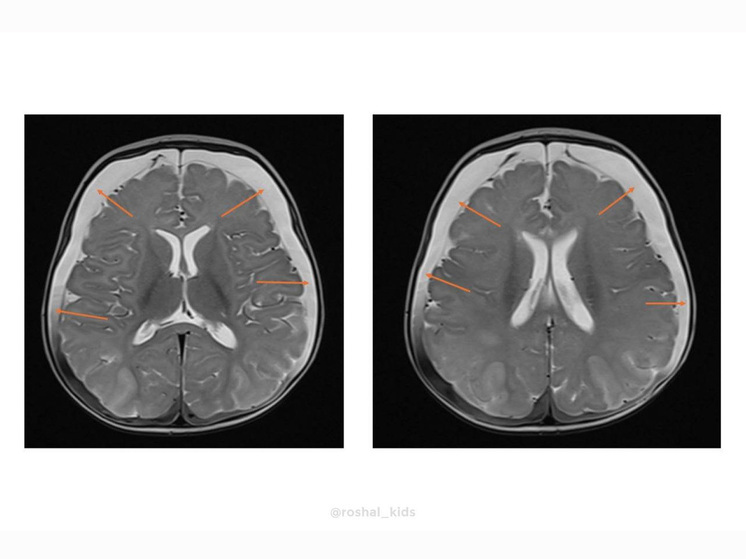

Как узнал «МК», в медучреждение в тяжелом состоянии привезли четырехмесячную девочку. У ребенка случился судорожный приступ. Обследование выявило пугающие симптомы: выпирающий родничок, увеличенный размер головы и критически высокий, почти в пять раз выше нормы, уровень аммиака в крови (194 мкмоль/л при норме до 47). Врачи выяснили, что у маленькой пациентки оказалось крайне редкое генетическое заболевание: ННН-синдром. Это нарушение цикла мочевины, врожденный сбой в обмене веществ. Организм не может перерабатывать белок, из-за этого происходит отравление аммиаком, буквально разрушающее мозг.

Специалисты подобрали терапию, которая помогла прекратить поступление белка. Это позволило предотвратить необратимое повреждение мозга. Уже через 24 часа уровень аммиака снизился до нормальных значений.